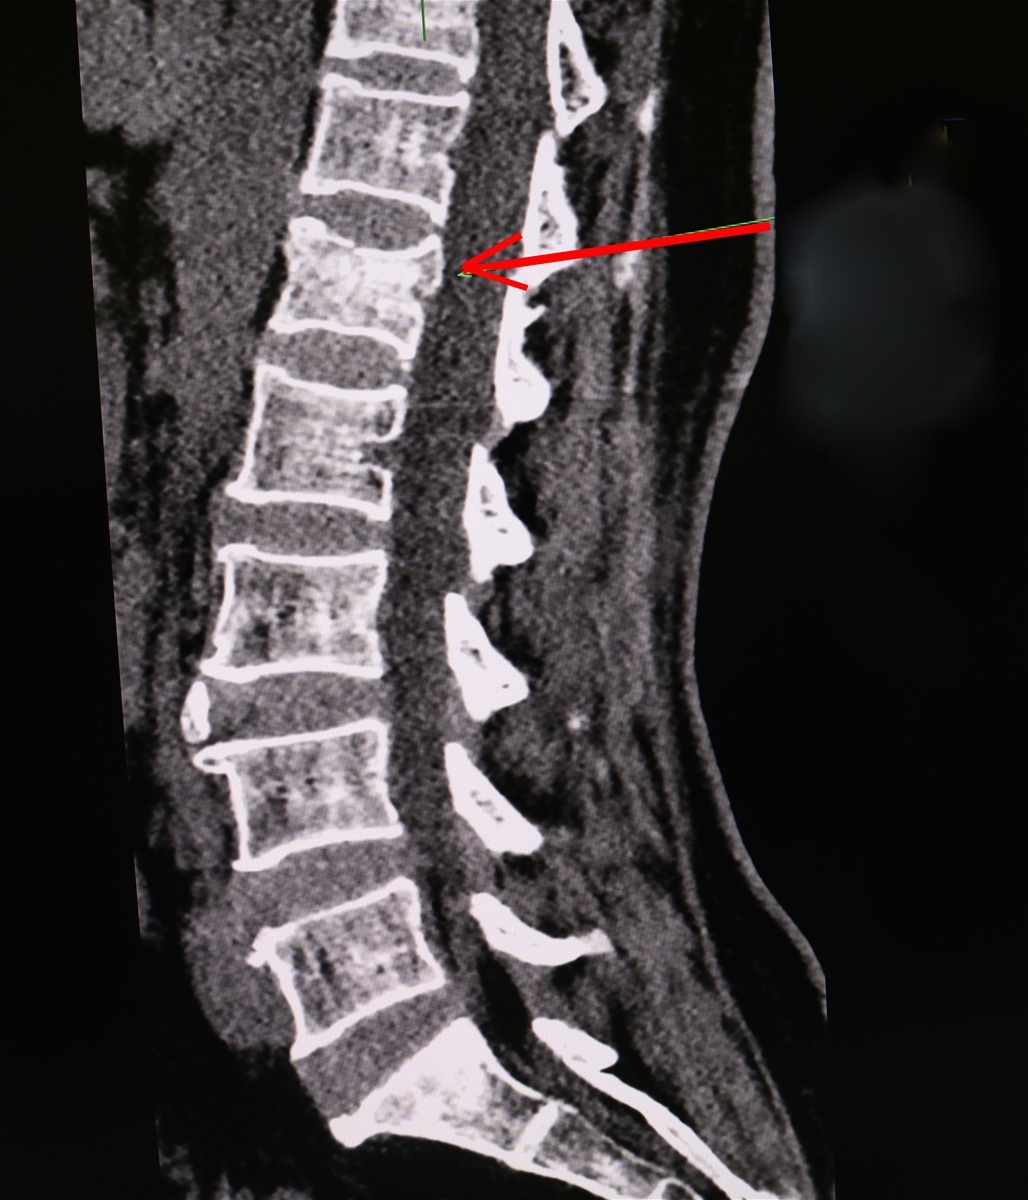

Hình ảnh xẹp đốt sống L1 của người bệnh. Ảnh: BVCC.

Thạc sĩ, bác sĩ Phạm Minh Phương, Trưởng khoa Ngoại Thần kinh, cho biết người bệnh được chẩn đoán vỡ mâm chày trái, xẹp đốt sống L1.